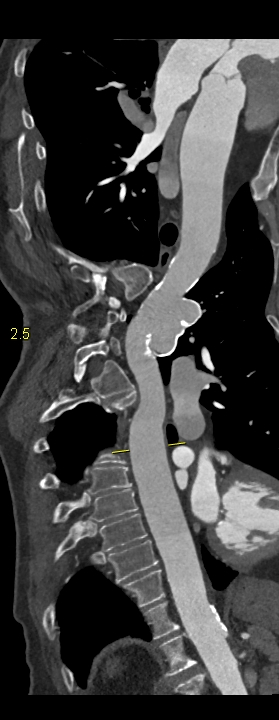

Figura 2: reconstrucţie aortică în planul vasului

Pacient cu traumatism prin accident de mașina în antecedente; efectuează examinare CT de artere coronare si aorta toracică. Se evidențiază un pseudoanevrism de istm aortic cu prezenta de calcificări arciforme pe contur.

Pseudoanevrismul de istm aortic este practic o ruptură conținută de aortă şi apare la pacienții care suferă un traumatism cu decelerare importantă. Deseori apare ca descoperire întâmplătoare tardivă, mai ales daca traumatismele au avut loc cu mulți ani in urma când examinarea CT nu se efectua de rutină la acest tip de pacienți.